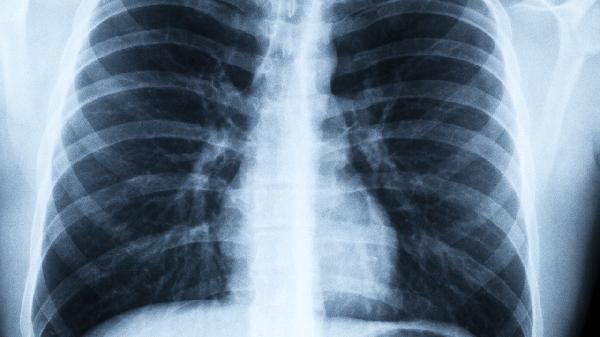

3、定期低剂量CT筛查

45岁以上长期吸烟者建议每年做一次低剂量螺旋CT,这种检查能发现直径2mm的微小结节,辐射量仅为常规CT的1/5。